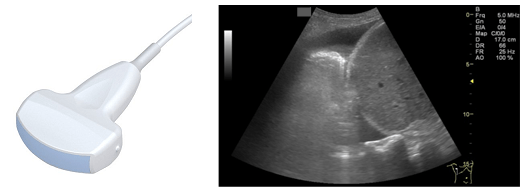

Dla ultrasonograficznej oceny typu point-of-care wykorzystać można każdy dostępny aparat USG. Oczywiście nowe, wielofunkcyjne urządzenia dają więcej możliwości diagnostycznych. Należy jednak unikać przekonania, iż określony aparat USG przeznaczony jest do konkretnego rodzaju badania. Jego możliwości diagnostyczne determinowane są przede wszystkim rodzajem wykorzystywanej głowicy. Głowice ultrasonograficzne działają w pewnym sensie jak „magiczne latarki” emitujące wiązkę ultradźwięków wnikającą w głąb ciała pacjenta. Fale odbite od napotkanych na swojej drodze struktur anatomicznych pozwalają na odwzorowanie na ekranie urządzenia dwuwymiarowego przekroju badanej okolicy. Aparat wykorzystywany dla oceny stanu nawodnienia powinien być wyposażony w co najmniej w głowicę typu convex lub sektorową (lub obydwa rodzaje). Głowice te różnią się nieco charakterystyką emitowanych ultradźwięków i kształtem czoła głowicy, dzięki czemu ułatwiają uzyskanie niektórych projekcji, ale w dużym zakresie można je stosować zamiennie.

Głowica convex pracuje w zakresie częstotliwości 2-8MHz, czoło tej głowicy ma kształt zakrzywiony, co przy linowym ułożeniu kryształów piezoelektrycznych sprawia, iż obraz generowany na monitorze USG ma kształt wycinka koła (Rys 1). Dzięki takim cechom głowica ta jest wysoce uniwersalna. Cechuje się dobrą rozdzielczością w bliskim polu i głęboką penetrację wiązki ultradźwięków – nawet do 30cm. Najczęściej jest używana do badania jamy brzusznej, gdyż pozwala uzyskać szeroki kąt wizualizacji. Głowicy tej można także użyć do oceny serca lub dla monitorowania przebiegu procedur inwazyjnych niewymagających dużej precyzji.

Głowica sektorowa jest pod względem parametrów fizycznych bardzo podobna do głowicy convex. Pracuje ona w podobnym zakresie częstotliwości i co za tym idzie oferuje podobny zakres penetracji. Różni się znacząco kształtem czoła głowicy. Jej budowa pozwala na uzyskanie szerokiego pola skanowania przy małej powierzchni kontaktu z ciałem pacjenta (Rys 2). Ułatwia to badanie serca przez wąskie okna akustyczne, jakimi są międzyżebrza. Doskonale nadaje się również do badania jamy brzusznej (badania dużych narządów w środkowym i dalekim polu głowicy).